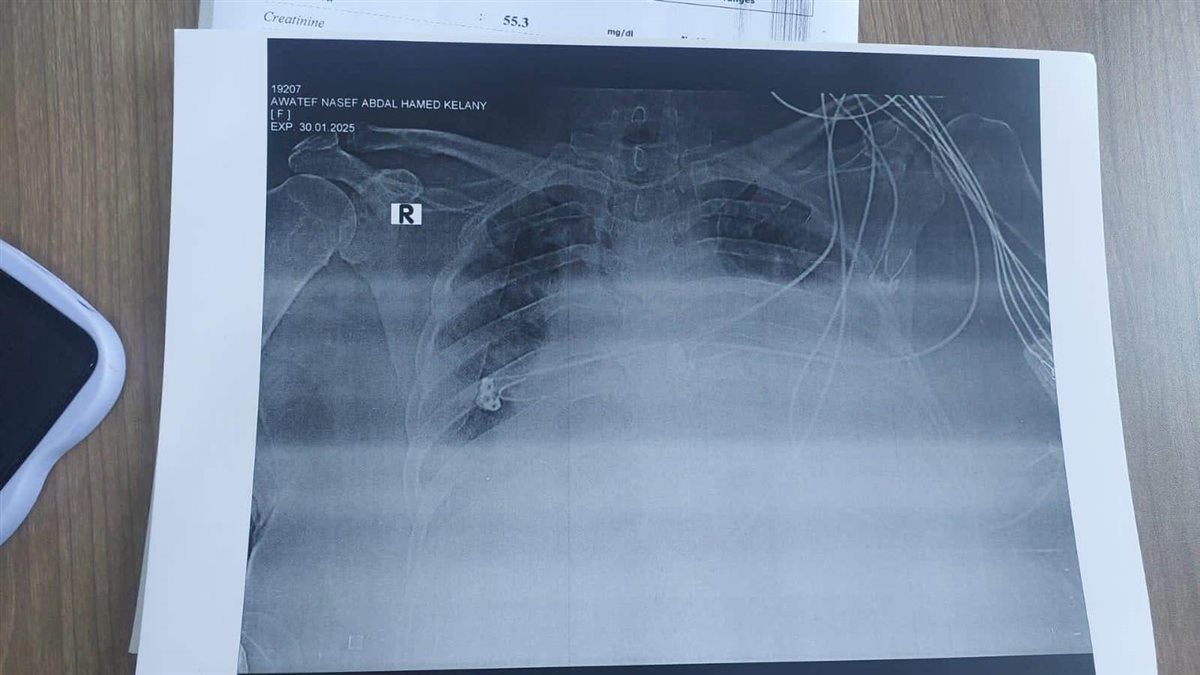

نجح فريق طبي متميز بمستشفى صدر دمنهور ، بإجراء عمل بزل طارئ لغشاء التامور للقلب وتركيب درنقة، لحالتين وذلك لأول مرة، دون الحاجه لتحويل الحالات للمستشفى الجامعي بالإسكندرية.

تم إدخال الحالات لقسم العناية المركزة، تبلغ الحالة الأولى من العمر ٥٠ عاما وتعاني من التهاب رئوي مصاحب، والأخرى ٦٩ عاما وتعاني من أعراض التهاب رئوي ودرن رئوي.

وتم التدخل الطارئ لاستشاري جراحة القلب والصدر الدكتور مسعد محمود عبدالله، وأخصائى القلب والقسطره القلبية ،الدكتور خالد أحمد الشرنوبي، ومدير العناية المركزة، الدكتور أحمد عبدالعزيز سليمان ونائب مدير العناية المركزه الدكتور محمد بسيوني سليم، ومشرفة العناية شيماء حسن محمد.